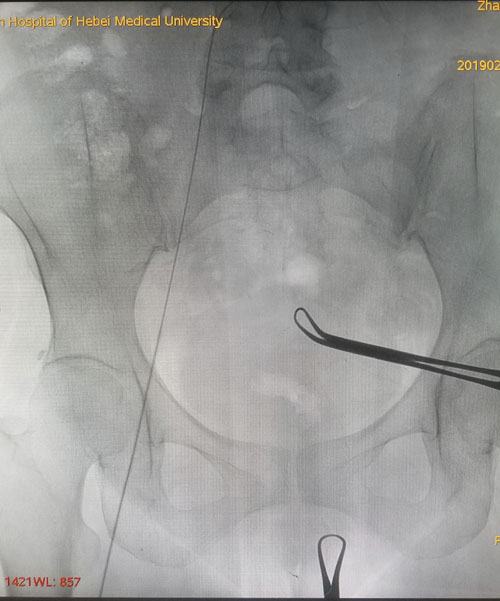

术中DSA评估导丝走形